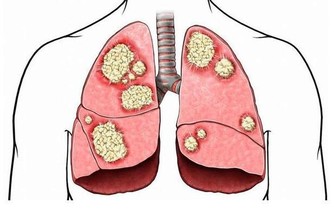

痛風,是由於體內嘌呤代謝紊亂所引起的一類疾病。因其起病急驟,來勢如風,疼痛劇烈,多伴紅腫,走時較快,不留影蹤,故名痛風。該病的臨床特點是高尿酸血症,及由此引起的痛風性急性關節炎反復發作、痛風石沉積、痛風石性慢性關節炎和關節畸形。常累及腎臟引起慢性間質性腎炎和尿酸性腎結石,並引起腎功能損害,累及血管可以引起高血壓,累及心臟可以引起冠心病,並且常常伴發高脂血症、糖尿病等疾病。

因此,儘管痛風多表現在關節引起關節炎,但實際上它是一種全身病變,可引起多髒器損害,甚至危及生命,因此,必須引起高度重視。